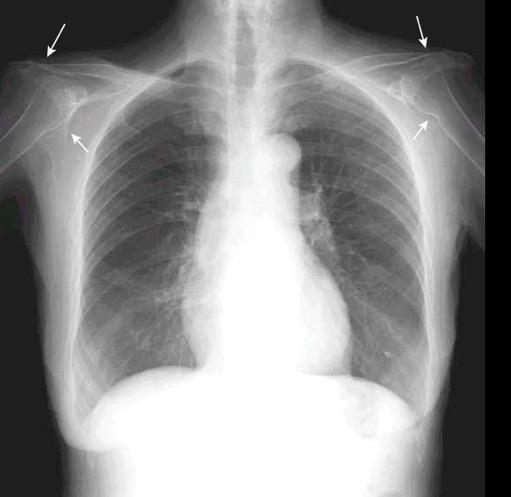

Hallazgo temprano: Osteopenia general. Erosión marginal del borde inferior de la cabeza humeral.

Osteólisis del extremo externo de la clavícula.

Cuomo F et al. THE RHEUMATOID SHOULDER.

Rheum Dis Clin North Am . 1998